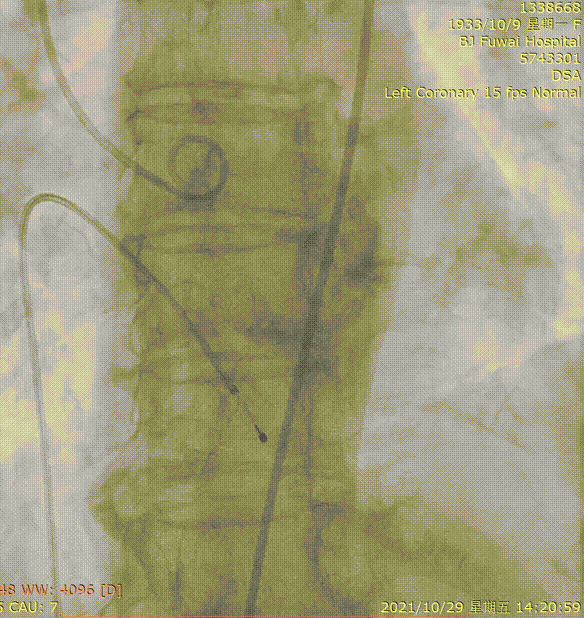

1.冠脉造影及介入治疗

左冠造影